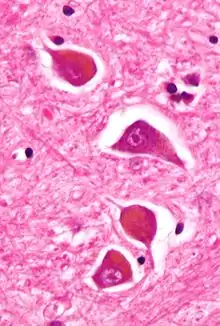

Micrograph of Alzheimer type II astrocytes, as may be seen in hepatic encephalopathy. | |

There are various explanations why liver dysfunction or portosystemic shunting might lead to encephalopathy. In healthy subjects, nitrogen-containing compounds from the intestine, generated by gut bacteria from food, are transported by the portal vein to the liver, where 80–90% are metabolised through the urea cycle and/or excreted immediately. This process is impaired in all subtypes of hepatic encephalopathy, either because the hepatocytes (liver cells) are incapable of metabolising the waste products or because portal venous blood bypasses the liver through collateral circulation or a medically constructed shunt. Nitrogenous waste products accumulate in the systemic circulation (hence the older term "portosystemic encephalopathy"). The most important waste product is ammonia (NH3). This small molecule crosses the blood–brain barrier and is absorbed and metabolised by the astrocytes, a population of cells in the brain that constitutes 30% of the cerebral cortex. Astrocytes use ammonia when synthesising glutamine from glutamate. The increased levels of glutamine lead to an increase in osmotic pressure in the astrocytes, which become swollen. There is increased activity of the inhibitory γ-aminobutyric acid (GABA) system, and the energy supply to other brain cells is decreased. This can be thought of as an example of brain edema of the "cytotoxic" type.[12]